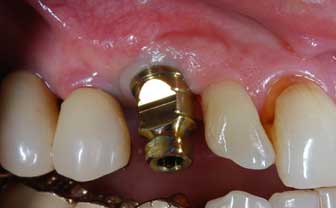

IMPIANTI POST-ESTRATTIVI

Impianto post-estrattivo

In un paziente cardiopatico di 72 anni